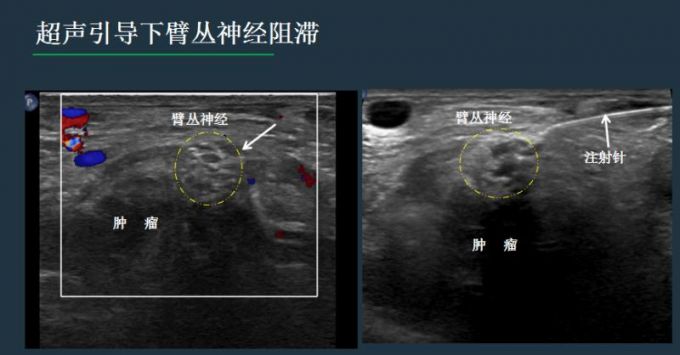

卢漫介绍说,神经的阻滞和毁损,既往多是凭体表解剖标记和医生的经验完成,由于神经的变异和不能看见穿刺针路径和针尖位置,易导致失败和意外。现在更多是在CT或超声引导下完成,但相比CT引导,超声无射线,通过屏幕上的实时显示,可以清晰看到穿刺针的路线,避开肠管、血管、骨头等,随时调整进针方向、深度,当针尖到达目标后,进行精准治疗。

同时,注射药物时,加上少量的超声造影剂,可以避免药物误入血管、直肠等重要组织,还可以实时评估药物的弥散范围,掌控用药分寸,预估效果。